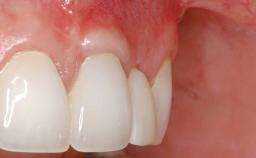

This case demonstrates that a connective-tissue graft in combination with a coronally positioned graft is an effective method of treating cases with peri-implant mucositis and an abutment-level sinus abscess. A 42-year-old man presented with a swelling adjacent to an implant crown at site 21. The swelling had been present for approximately three weeks and was constrained to the buccal and palatal gingival aspects of the implant. A discharge was noted on finger pressure, with localized gingival recession present on the mid- and distolabial aspects of the crown.

Soft Tissue Grafting Staged